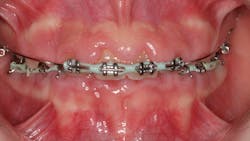

One reason people develop gummy smiles is inflammatory-induced gingival enlargement, typically caused by biofilm (bacteria) and the host response. Gum disease (gingivitis and periodontitis) can result in gum tissue swelling, redness, gum overgrowth, and bleeding (figure 1). In addition to bacterial infiltration of the gums due to poor oral hygiene, orthodontic appliances have been associated with gingival enlargement since braces can act as food traps (figure 2).Further reading: Considerations when using veneers to fabricate a perfect smile